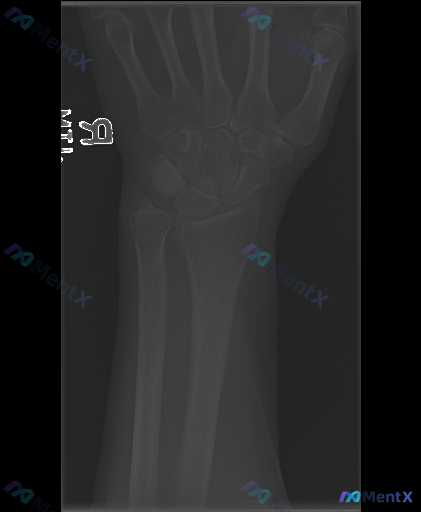

整理到一张右侧手腕正位X光片资料,大家看看影像表现更支持哪些判断?

整理到一张右侧手腕X光正位片的影像资料,先把关键表现列出来,大家看看这种情况第一反应会往哪些方向考虑?

- 桡骨远端关节面可见横行透亮骨折线,累及关节面,骨皮质不连续,骨折端无明显移位;

- 尺骨茎突可见撕脱性骨折征象,骨折块位置清晰;

- 舟骨、月骨、三角骨等腕骨骨皮质连续性尚可,未见明显骨折线或移位;

- 未见明显应力性骨折线或骨膜反应。

- 桡腕关节间隙对位尚可,受桡骨远端骨折影响,关节面平整度略受干扰;

- 下尺桡关节间隙未见明显脱位/半脱位;

- Gilula弧线基本保持平滑,未见明显腕骨脱位或排列紊乱;

- 舟月间隙及其他腕骨间隙未见明显异常增宽。

- 腕关节周围软组织影轻度肿胀,密度较均匀;

- 关节腔及周围软组织未见明显游离骨块、异物或异常钙化;

- 未见明显骨赘、关节间隙狭窄等退行性变,也未见骨质侵蚀/破坏。